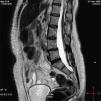

Presentamos el caso clínico y el estudio radiológico de una mujer de 57 años remitida a nuestro servicio de rehabilitación por presentar una mielopatía cervical con una escoliosis dorsolumbar detectada en la preadolescencia; clínicamente presentaba deformidades ortopédicas con manifestaciones neurológicas, aunque sin alteraciones cutáneas claras.

We present the clinical case and radiological study, of a 57 year-old woman remitted to our rehabilitation service in order to introduce a cervical myelopathy with a scoliosis lumbar back detected in young people, clinically it presents orthopedic deformities with neurological manifestations although without cutaneous clear alterations.